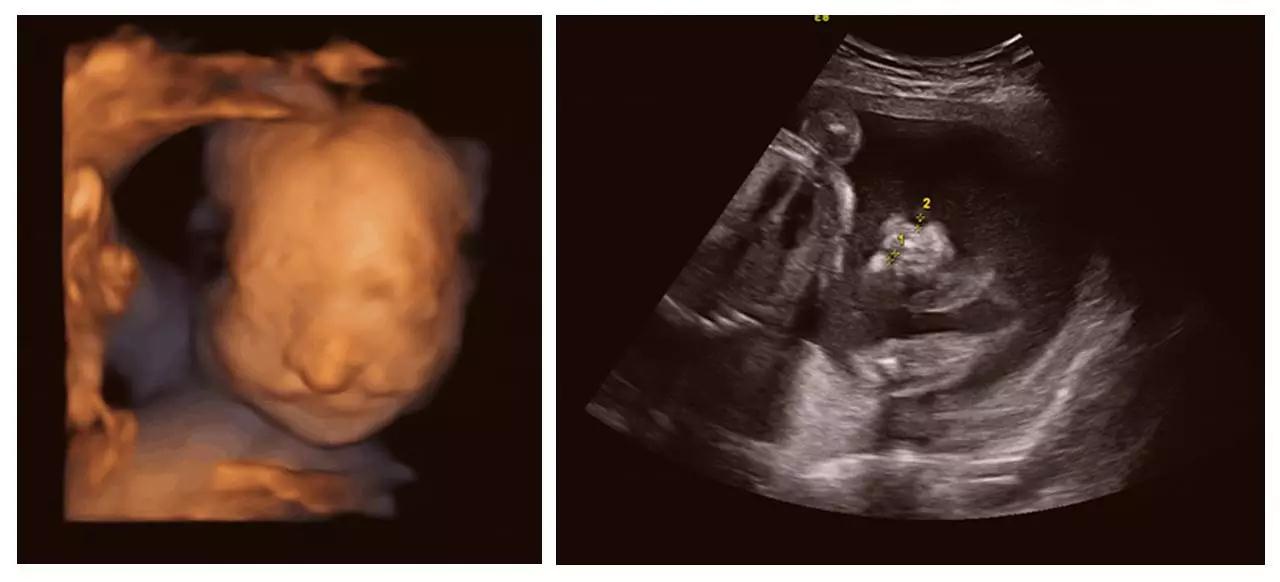

美GE不仅能提供包括腹部、血管、小器官、产科、妇科、泌尿科、新生儿和儿科等多领域的多方面的应用,而且能够显示未出生的宝宝的实时动态活动图像,为胎儿进行宫内拍“写真”和动态录像,让宝宝拥有完整的0岁相册。通过四维彩超(四维彩超),可以看到宫内胎儿打哈欠、伸懒腰、吮手指等萌萌的动作,让准爸妈们增添了安心和乐趣,不再仅仅是感觉宝宝的呼吸和运动,可以亲眼目睹宝宝的举动和乖巧容颜。还可以打印宫内高清写真,作为送给未来宝宝的珍贵礼物!

(左心发育不良)

(胸腹腔积液、全身水肿)